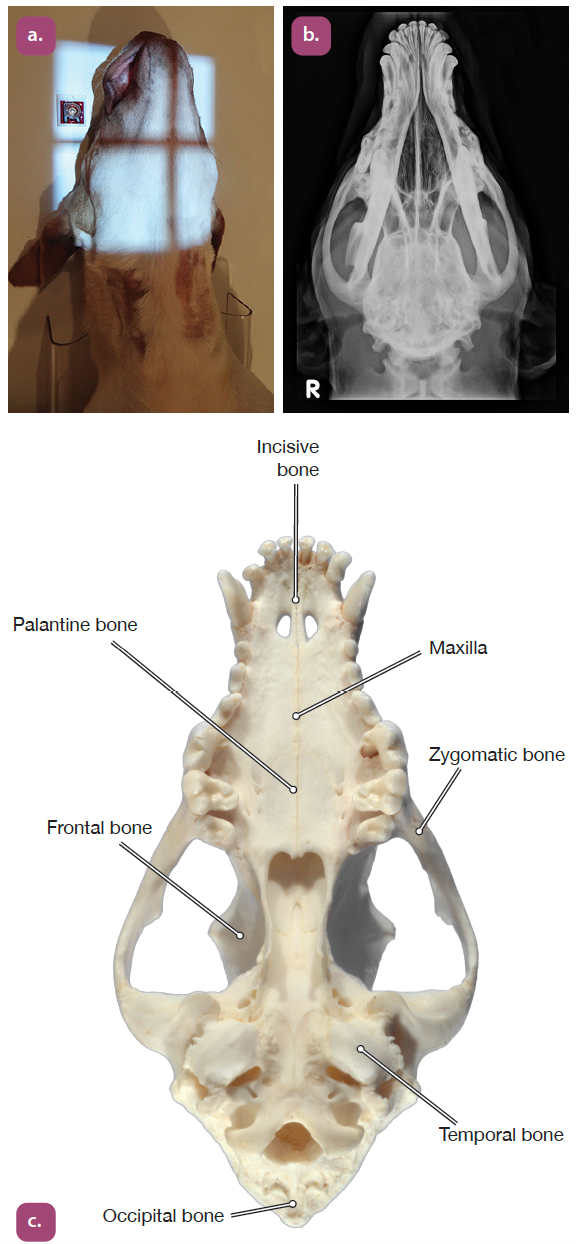

ventrodorsal projection of the skull